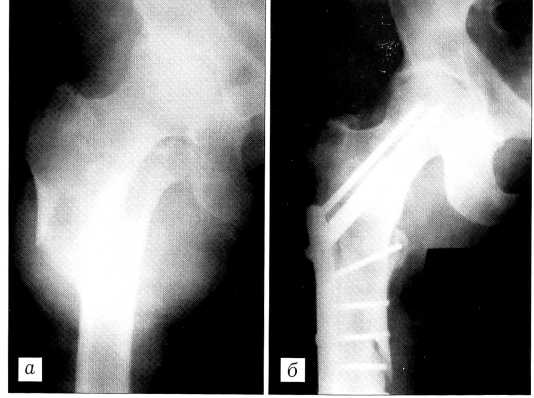

Больная Ц.,84 лет, поступила в отделение 28.03.99 через 3 ч после травмы (падение на улице). Диагноз: закрытый чрезвертельный перелом правой бедренной кости со смещением отломков 31 А2.2. Сопутствующий диагноз: ишемическая болезнь сердца; атеросклеротический кардиосклероз Н2; атеросклероз сосудов головного мозга; гипертоническая болезнь III стадии; хронический бронхит вне обострения; желчно-каменная болезнь, хронический калькулезный холецистит. 31.03.99 под перидуральной анестезией произведен остеосинтез бедра компрессирующим устройством. Больная выписана из отделения через 16 сут после травмы. Спустя 3 мес после операции оставила костыли и начала ходить с тростью. При осмотре через 4 мес: полное восстановление функции оперированной конечности; пациентка обслуживает себя, выходит из дома на улицу, посещает поликлинику и магазины (рис. 5).

Рис. 5. Рентгенограммы правого тазобедренного сустава больной Ц. 84 лет. а - при поступлении: чрезвертельный перелом левой бедренной кости со смещением отломков, тип 31 А 1.2; б — после остеосинтеза.